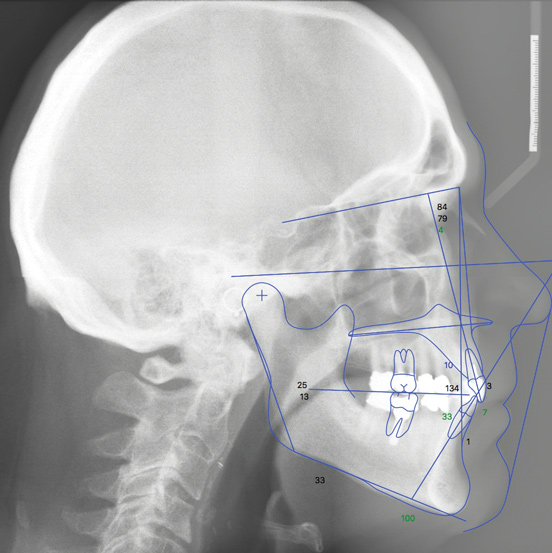

• Smile optimization. When optimizing the smile position of the upper anterior teeth, using cephalometric analysis can provide a more consistent evaluation than a subjective impression of underlying jaw and tooth relationships. Due to the excessive interincisal angle present in this case, the removable aligners were programmed with lingual root torque for the upper anterior teeth (Figure 5 and Figure 6).

(5.) Postorthodontic cephalometric analysis.

Figure 5